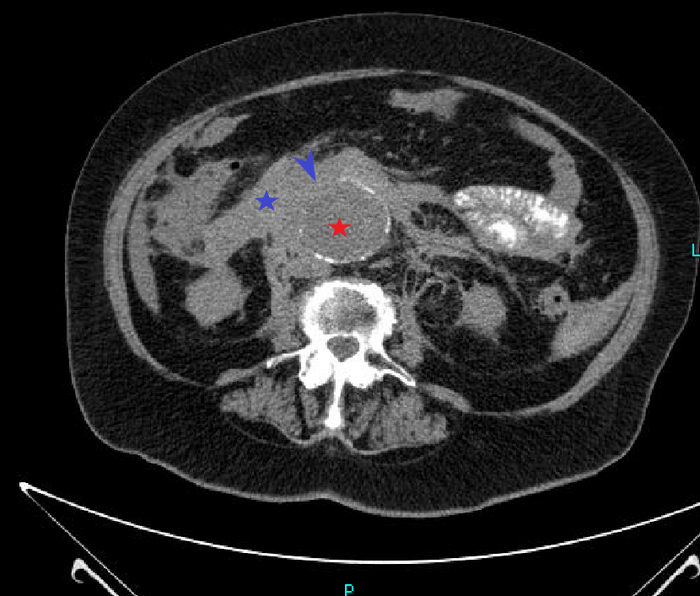

По КТ в мягкотканном окне (специальные настройки яркости и контраста для лучшего отображения мягких тканей) определялись увеличенные лимфатические узлы в средостении справа паратрахеально, в области корня правого лёгкого и инфракаринально (ниже места "разделения" трахеи на правый и левый бронх):

1 и 2: аксиальные срезы, 3 - корональная реконструкция; лмф.узлы - красные стрелки